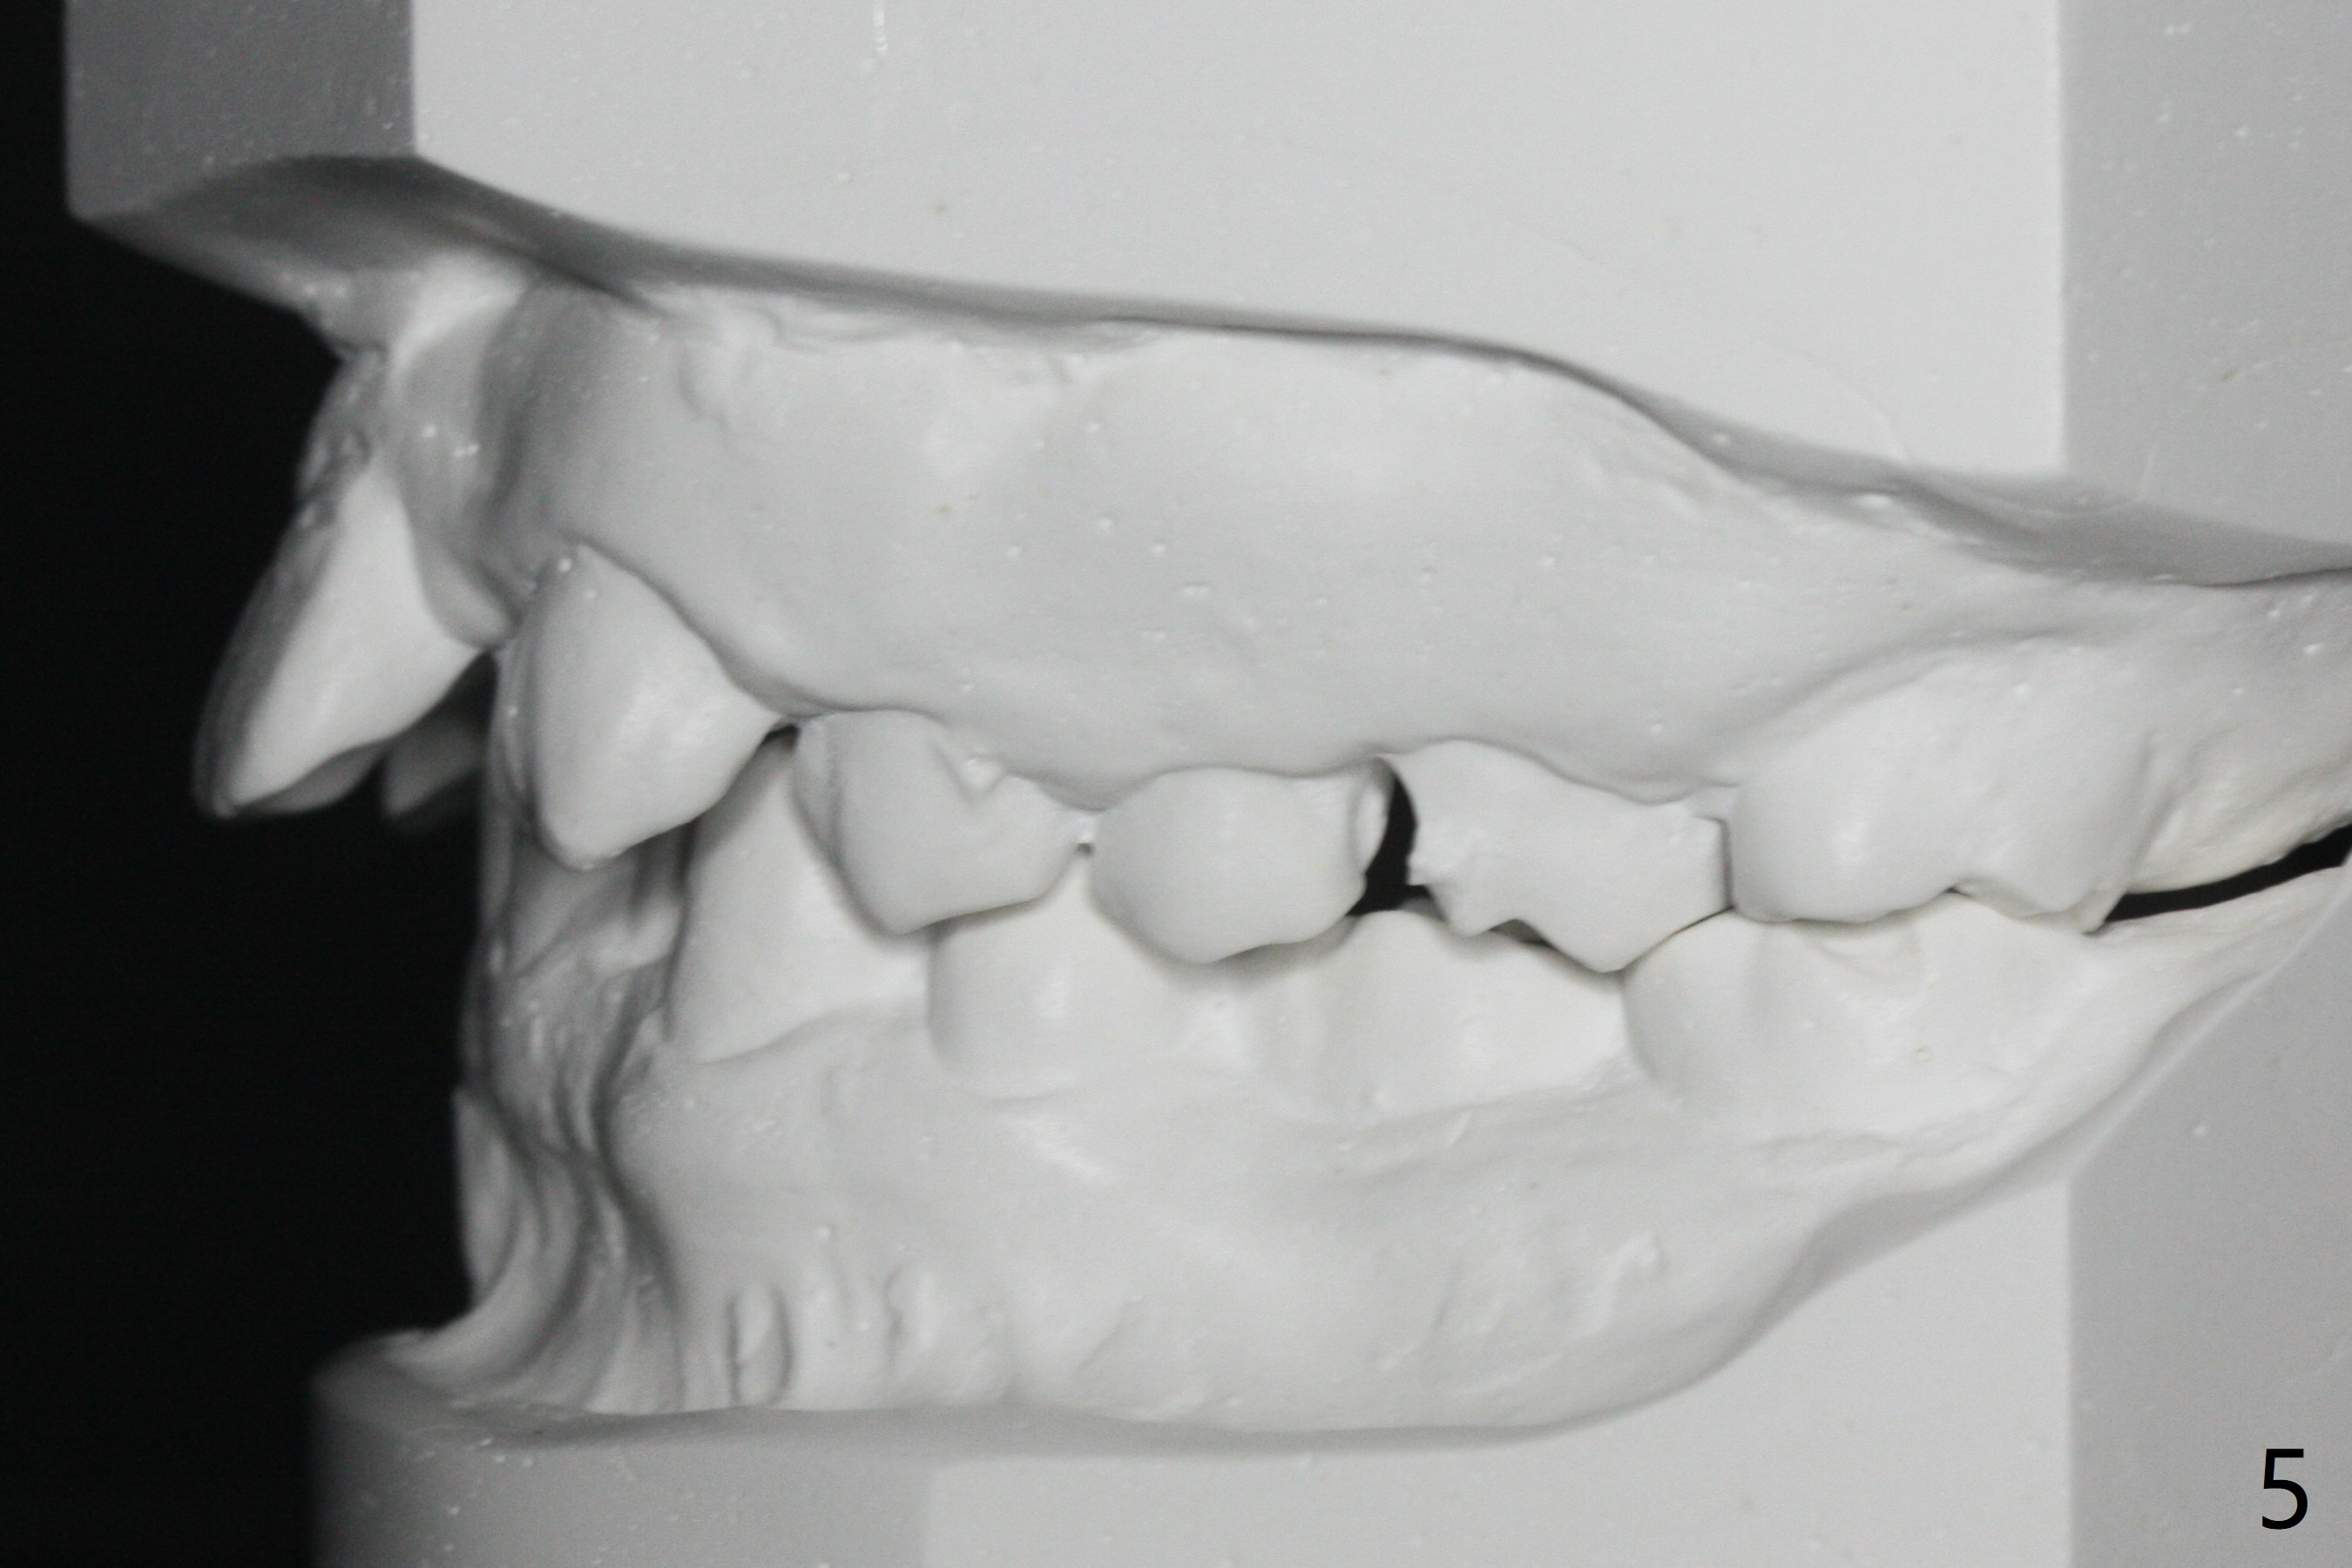

A 32-year-old man has had severe crowding for the last 10 years (Fig.1-5).  He is ready for orthodontic treatment now.  LL5 has been extracted for 4 years (Fig.1 x).  Severe caries at UR5 makes it easy to decide for extraction (Fig.2 x), while it is hard to determine which of the LR bicuspids needs to be extracted because of moderate caries at LR5 and even harder for UL because of caries at UL6,7 (Fig.2 *).

In fact impression for models (Fig.3-7) is taken after UL caries control.  Sedative filling is done at UL1,3 (Fig.6 *) and definitive restoration will be done when crowding resolves.  The defects at UL6,7 (Fig.6 x) is so extensive that after composite molar bands are placed immediately for retention.  Amazingly, there is no symptom after UL6,7 restoration.  Therefore UL4 will be extracted for crowding resolution.  UR 5 (Fig.1-3,6) has been extracted, while LR5 (Fig.2,7) will be.